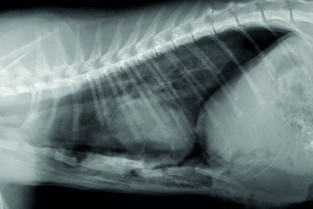

Adopter une méthodologie pour interpréter les affections de la cage thoracique, de la plèvre, du médiastin et des poumons chez les carnivores domestiques.

- Décrire l’aspect normal et anormal de la cage thoracique, de la plèvre, du médiastin et des poumons chez les carnivores domestiques.